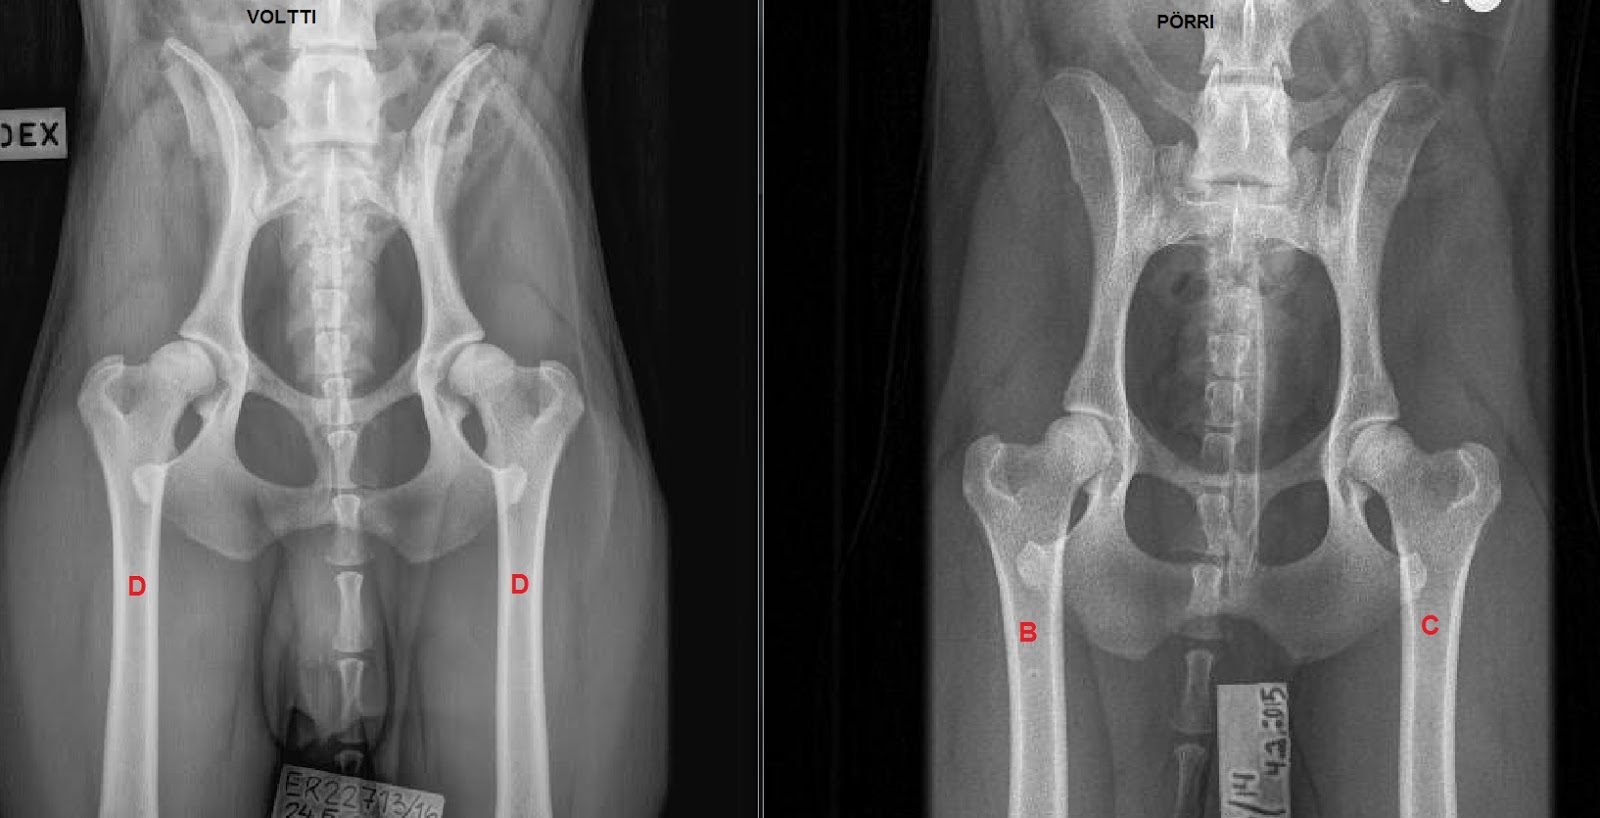

Kaaponkujalla Voltin Luustokuvat

Koiran lonkat c c. Koiraa jonka lonkat on arvioitu kirjaimella d tai e vakava asteisia muutoksia lonkkanivelissä ei tulisi käyttää jalostukseen. 7v rotikalla taas c d lonkat erittäin paha nivelrikko. 1 2 go to page. Koiran lopullinen tulos on huonomman puolen mukainen.

Koiran lonkkakuvaus tulokseen vaikuttaa koiran sen hetkinen tila eli onko koira jo täysin kehittynyt luustoltaan ja nartuilla hormonitoiminta joka jonkun verran juoksun aikana löystyttää nartun lonkkia tulokseen vaikuttaa myös lonkat kuvanneen eläinlääkärin tarkkuus ja viitseliäisyys. Jalostusvalintojen tekemistä helpottamaan on kehitetty blup indeksi eli jalostusarvoindeksi. Liz 08 03 2008 1 olen aikeissa ottaa koiranpennun keväällä emo siis nyt raskaana. Lonkat a b vasen lonkka a oikea b ja kyynärnivelet 0 0 molemmat terveet.

Mutta jos puhutaan vaikka labbiksista joilla on selvästi ongelmia lonkkien kanssa ei lähtisi käyttämään c lonkkaista ellei koirassa olisi jotain todella erikoista. Siinä otetaan huomioon koiran oman lonkkakuvaustuloksen lisäksi sen sukulaisten. Emon lonkat on c c eli ei kovin hyvät isällä onneksi a a. Koiranpennulla on syntyessään normaalit lonkat.